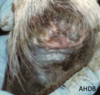

what is interdigital dermatitis (scald)

what are the clinical signs of interdigital dermatitis

Very painful

Moist

Hairless

White or pink

Ulcerated